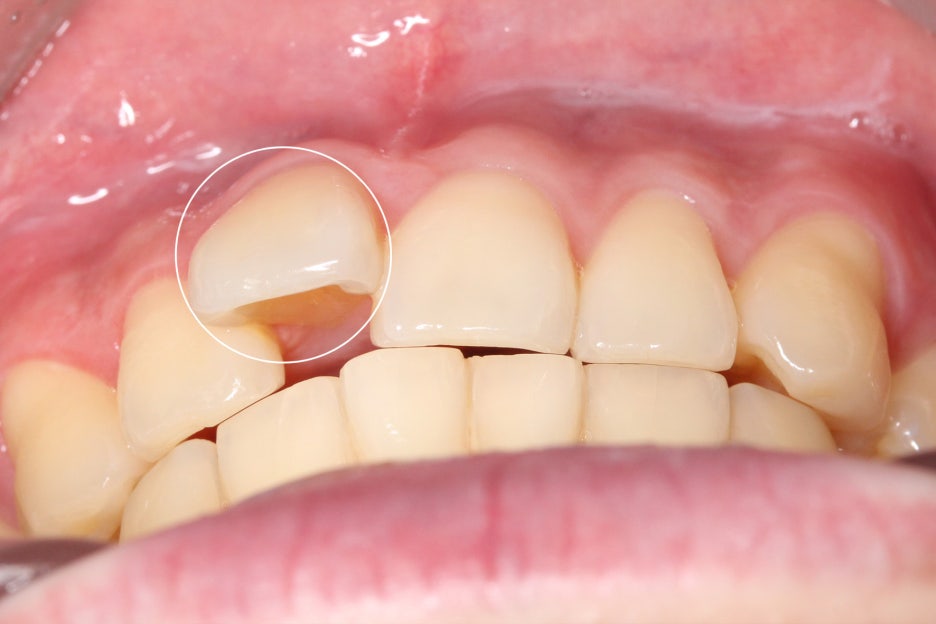

전치부를 약간 아랫쪽에서 바라본

overbite 사진에서도 정중선이

변위되어 있는 모습입니다.

또한 중절치가 가지런하게

배열되어 있지 않고 뻐드러지듯

돌출된 모습을 확인할 수 있는데요,

측면에서 overjet을 보면 중절치의

돌출 증상이 심한 모습으로 상악이

전방으로 뻐드러져 있어 입이 튀어나와 보이고

자꾸 입이 벌어지는 습관이 생길 수 있습니다.

이러한 경우 돌출된 앞니나 전치부를

교정하여 돌출감을 완화할 수 있어요.

2mm를 넘을 경우 돌출이 있다고 판단되기 때문에

치아를 교정하는 것이 좋습니다.